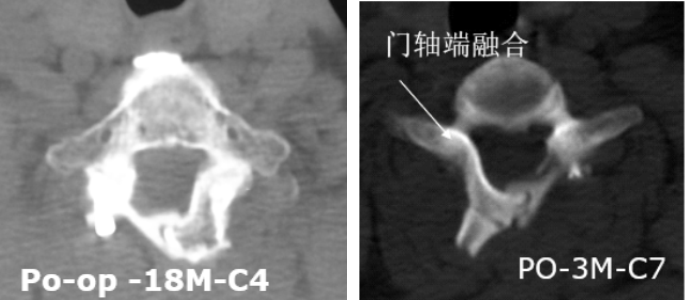

4.可融合,远期稳定性好